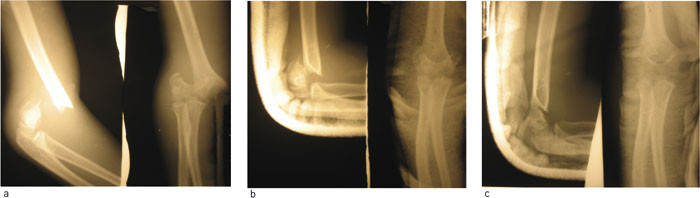

Figur 1 viser røntgenbilder av en av våre pasienter. Kontrollrøntgen etter en uke viste forhold som etter siste reponering, og det samme etter tre uker, da gipslasken ble fjernet. Pasienten fikk ikke optimal medisinsk behandling ut fra norske forhold, men den enkle behandlingen som er tilgjengelig her. Resultatet var likevel klart bedre enn det ville vært uten behandling, og det er godt håp om at han blir arbeidsfør i begge armer. For de fleste barn som får slik fraktur her i Nepal, er det en skade direkte relatert til deres daglige arbeid. De innlegges etter å ha falt ned fra trær eller utfor stup mens de har samlet fòr til familiens husdyr (fig 2). Ubehandlet gir disloserte suprakondylære humerusfrakturer redusert evne til manuelt arbeid resten av livet, en katastrofe i et samfunn der manuelt arbeid gir livsgrunnlag for de fleste.